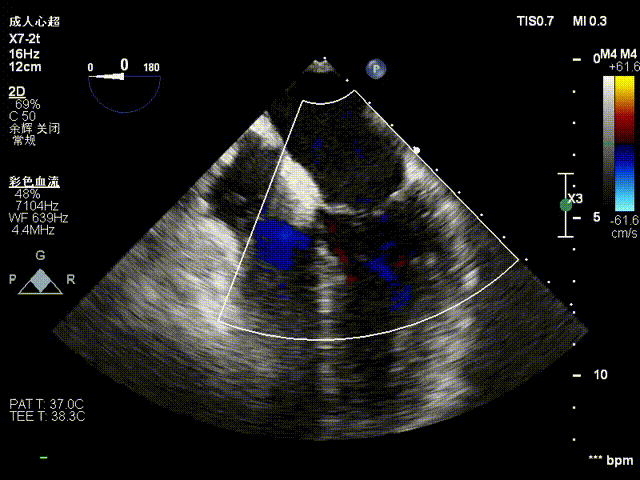

在术者的细致操作下完成瓣叶捕获,再度确认夹合器orientation后操作Gripper down,关闭C6后评估反流量微量即操作解离。影像下显示植入一枚C6可见3区反流明显下降,改善效果明显。

关夹合器

关夹合器评估

夹合后反流评估

检查示组织桥明显,夹合器稳定,残余反流明显减少,降低至1+等级,二尖瓣平均跨瓣压差为2mmHg,经团队评估,手术效果达既定预期,各项指标平稳,顺利结束手术。